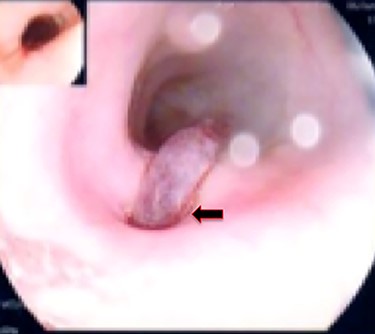

A 36-year-old male, involved in a minor motor vehicle accident while driving his car. He lost consciousness following a sudden onset of transient loss of vision which was not associated with palpitation or dizziness. His previous medical history revealed arterial hypertension and a corrected aortic coarctation with interposition graft at the age of 14. Pan CT scan was unremarkable except for thickening of the desending throacic aorta. His white blood count was very high (68 000 per cubic millimeter of blood). One day after the car accident, he developed nausea, hematemesis and melana. Upper GI endoscopy revealed blood in the stomach and distal esophafgus with no identifiable source of bleeding (Fig. 6). The patient developed massive hematemsis with hypotension requiring intubation and resuscitation. Another CT scan showed air pocket around distal aorta and contrast extravasation to the esophagus (Fig. 7). Another endoscopy revealed distal esophageal ulcer with clot extending toward the stomach (Fig. 8). AEF was suspected and then confirmed by aortogram. The fistula was treated by TEVAR (20 mm × 11.5 cm Valiant covered stent - Medtronic company, USA) followed by fully covered esophageal stent in the middle of the esophagus (Fig. 9).

The esophageal stent had been removed after 2 weeks. Six hours after stent removal, the patient showed again signs of active GI bleeding. Another upper GI endoscopy revealed superficial oozing from the site of the esophageal stent which was treated with cauterization and endoclip. Two month later, the patient was discharged with the recommendation for lifelong antibiotic therapy (Trimethoprim/sulfamethoxazole 800/160 mg) if no definitive reconstruction surgery done and Aspirin 100 mg. Three follow-up CT scans did not show any new pathology. Apart from one occasion of fever, the patient was doing well on regular outpatient clinic follow-up and he declined definitive surgery.